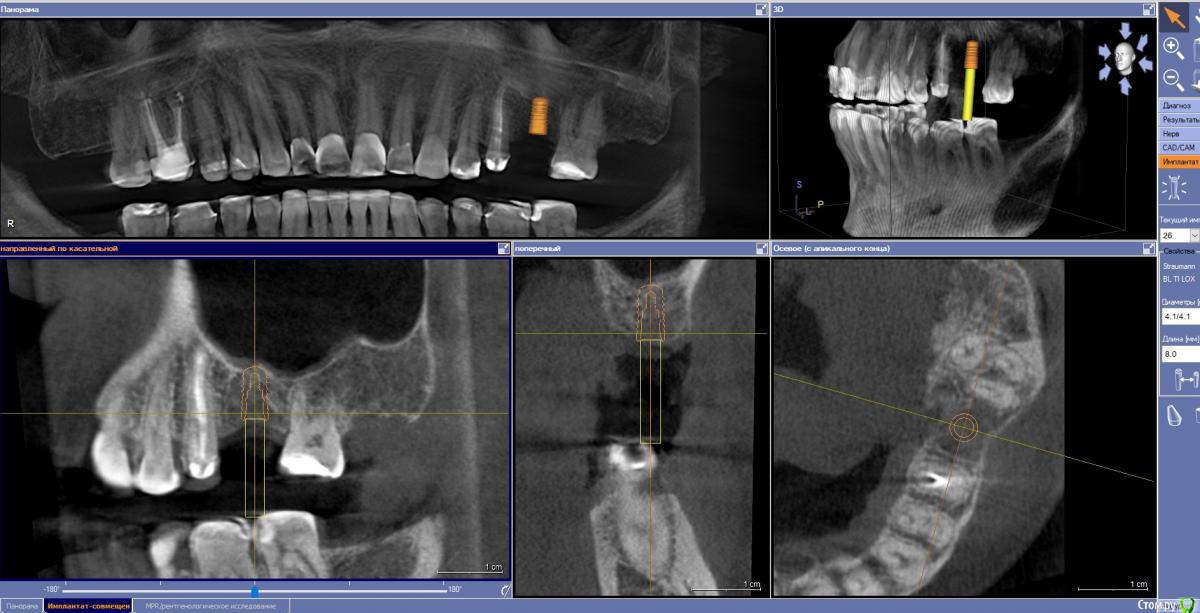

Ponchik Опубликовано 24 октября, 2017 Поделиться Опубликовано 24 октября, 2017 Как лучше поступить? Поставить покороче Альфа-Био 4.65-6 или Штрауманн 4.1-8 и постучать?Ортопеду всё равно, а я не могу определиться. Хочется поставить таки Штрауманн, но может это во мне жадность говорит и я всё усложняю? Ссылка на комментарий

red_butler Опубликовано 24 октября, 2017 Поделиться Опубликовано 24 октября, 2017 8 мм Ссылка на комментарий

ivanov6988 Опубликовано 24 октября, 2017 Поделиться Опубликовано 24 октября, 2017 Бикортикально 8 Ссылка на комментарий

Jurai Опубликовано 24 октября, 2017 Поделиться Опубликовано 24 октября, 2017 8 и стучать не придется. 4 Ссылка на комментарий

Ponchik Опубликовано 24 октября, 2017 Автор Поделиться Опубликовано 24 октября, 2017 Возьмите Штрауманн 4.1х6 Со стандартом или стандартплюс не работал пока. Профильных сверл пока под них нет даже 8 и стучать не придется. Мне кажется 8 полностью не влезет, часть гребня при препарировании уйдет. 1-1.5мм стукнуть надо (вроде) А кто вам мешает поставить альфа био 4.2 на 8? А смысл? 8 у альфы короче чем 8 у штрауманна за счет формы апекса? Решил постучать и на это 5 2 причины (не связаны с клиникой):1) вредный пациент (так и стукнул бы )2) набор с остеотомами от штрауманна пылью покрылся. На самом деле больше интересует устойчивость таких 6мм товарищей от альфы, адекватно ли 4.2-6 или 4.65-6 в таком случае? Ссылка на комментарий

Чертков Александр Опубликовано 26 октября, 2017 Поделиться Опубликовано 26 октября, 2017 8мм без стука, 10 со стуком, ложе подготовить конденсорами, фдм, аугментация мягких тканей. 3 Ссылка на комментарий